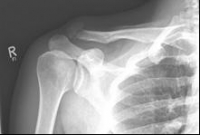

Picture 1                                                                Picture 2

Picture 1: Displaced fracture of the left collarbone before surgery.

Picture 2: After the operation, the fracture is correctly repositioned and held in position with a titanium plate and two screws..